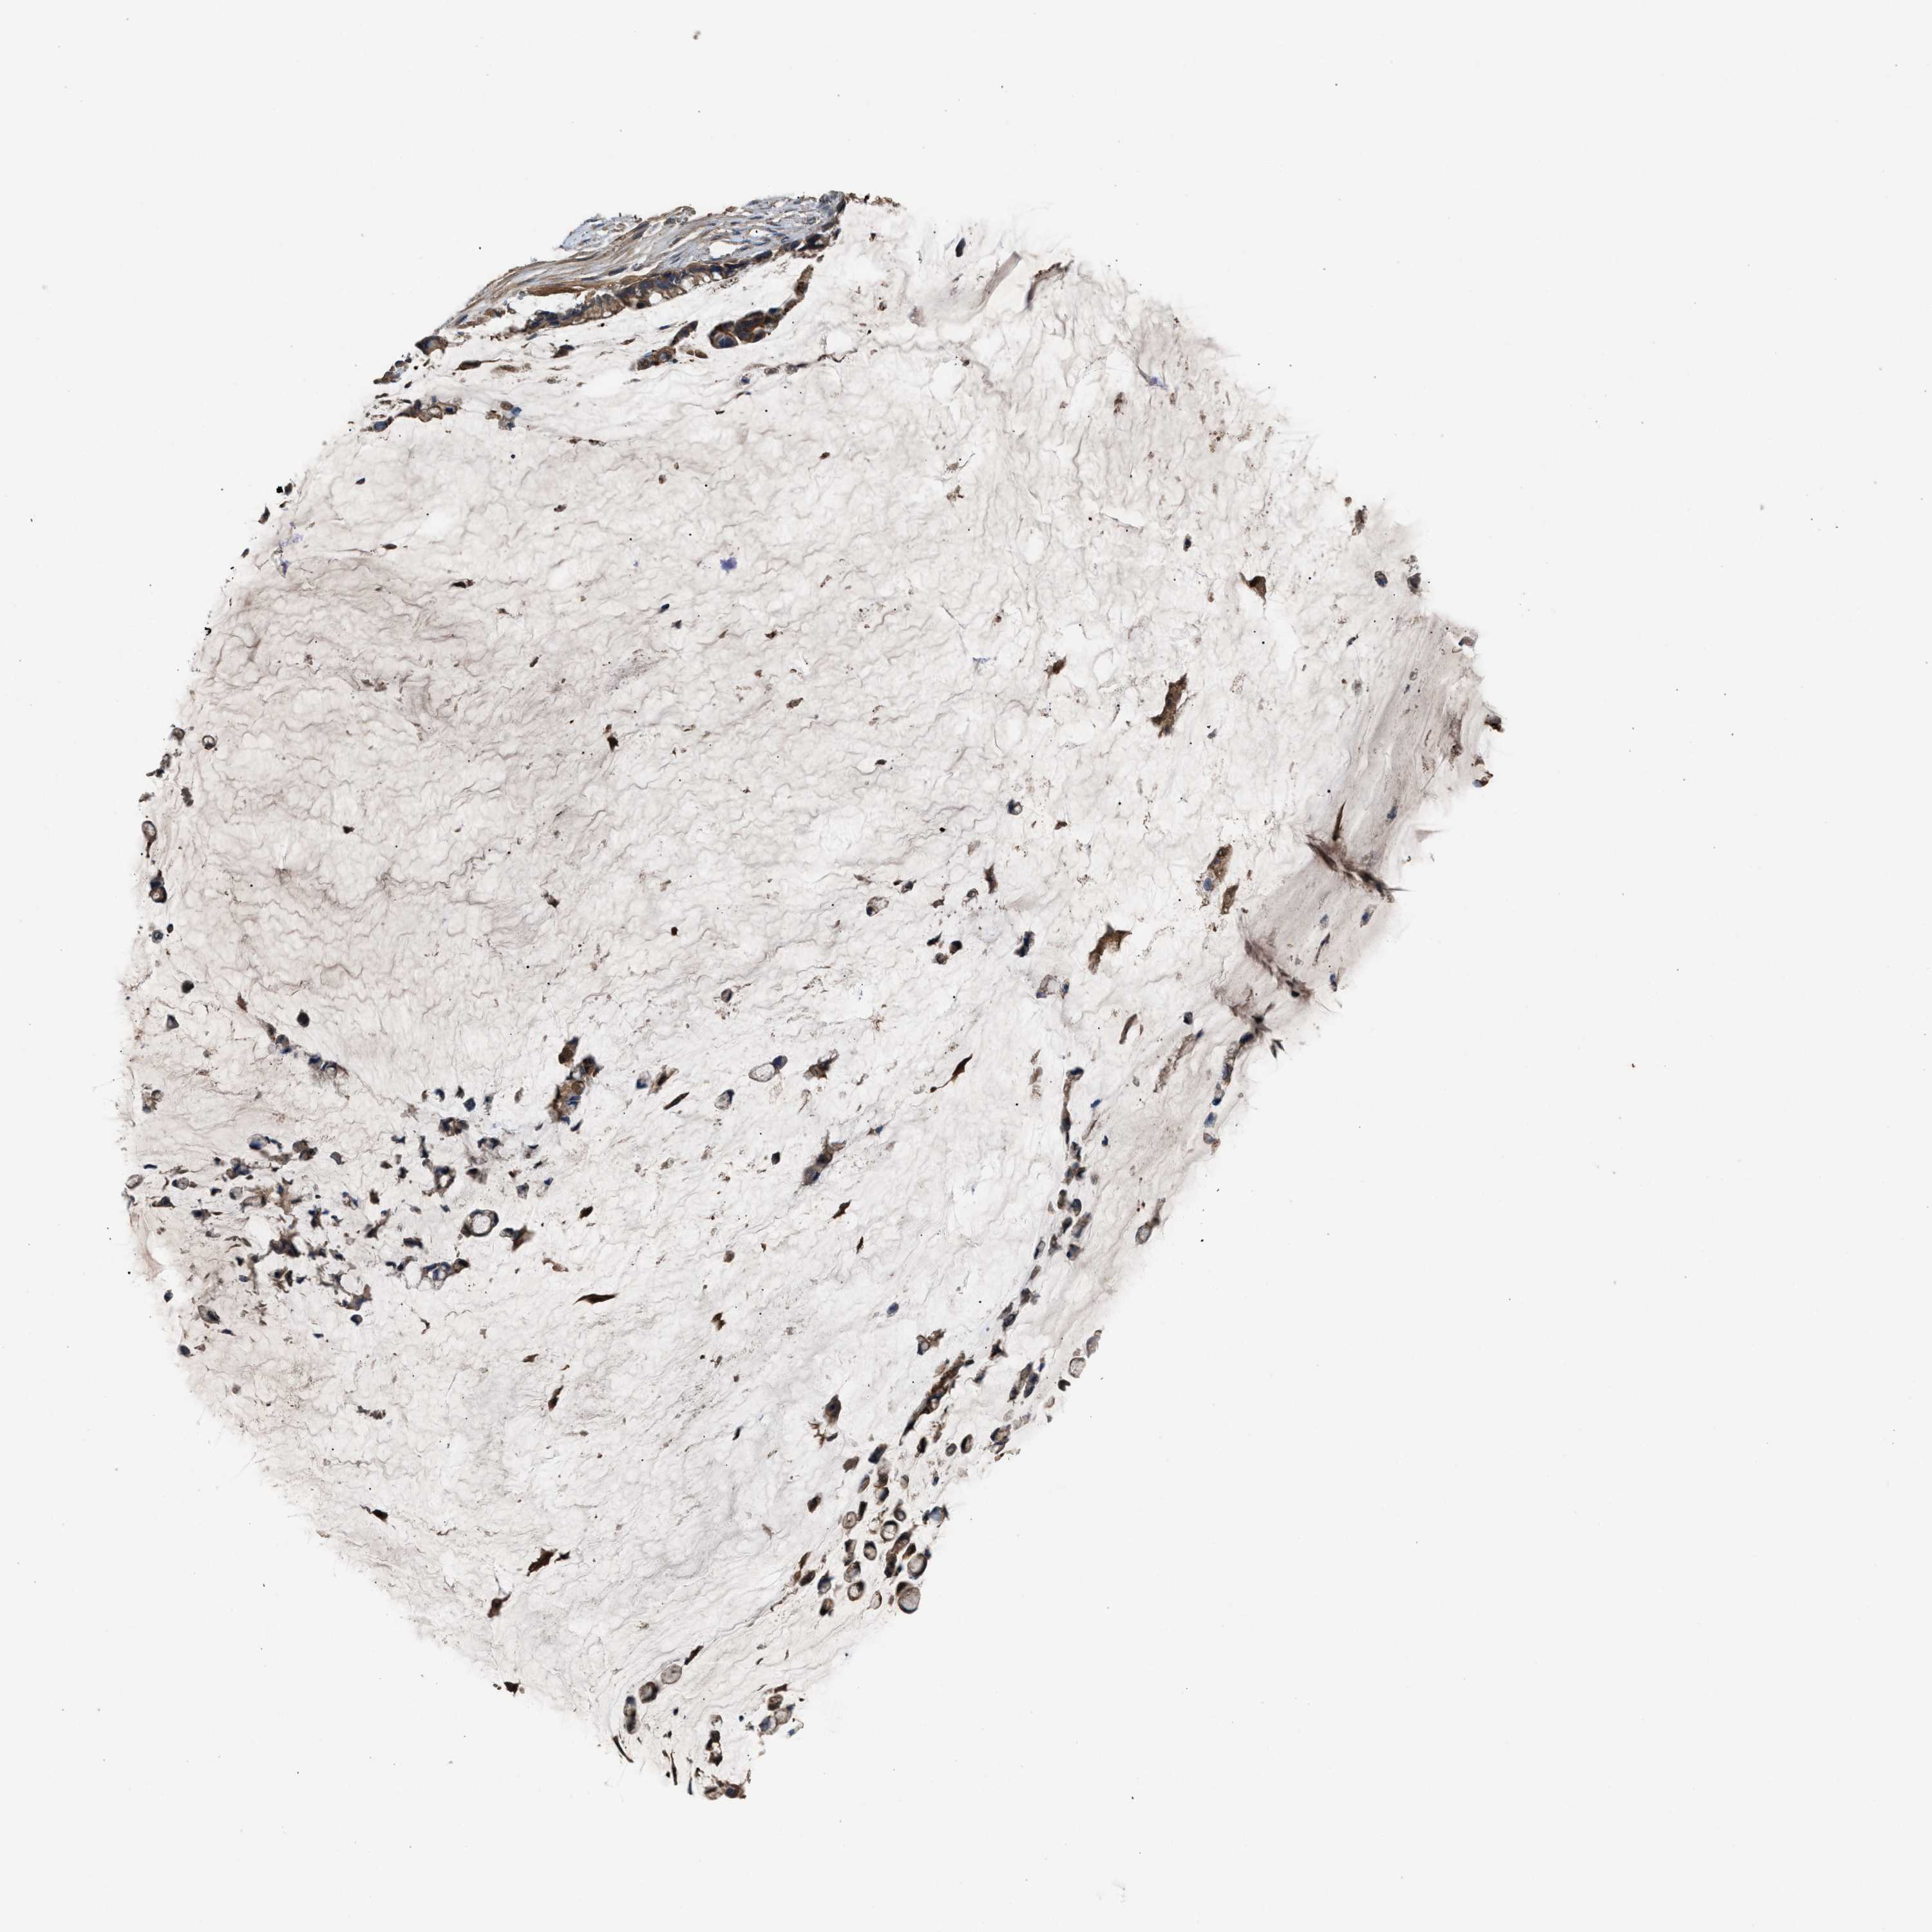

PANCREATIC CANCER - Protein expressioni

A mouse-over function shows sample information and annotation data. Click on an image to view it in a full screen mode. Samples can be filtered based on level of antibody staining by selecting one or several of the following categories: high, medium, low and not detected. The assay and annotation is described here.

Note that samples used for immunohistochemistry by the Human Protein Atlas do not correspond to samples in the TCGA dataset.

Antibody stainingi

Antibody staining in the annotated cell types in the current human tissue is reported as not detected, low, medium, or high, based on conventional immunohistochemistry profiling in selected tissues. This score is based on the combination of the staining intensity and fraction of stained cells.

Each image is clickable and will lead to virtual microscopy that enables deeper exploration of all samples and also displays staining intensity scores, fraction scores and subcellular localization as well as patient and tissue information for each sample.

Antibody HPA021545

Antibody HPA021849

Staining

High

Medium

Low

Not detected

Intensity

Strong

Moderate

Weak

Negative

Quantity

>75%

75%-25%

<25%

None

Location

Nuclear

Cytoplasmic/membranous

Cytoplasmic/membranous,nuclear

Adenocarcinoma, NOS